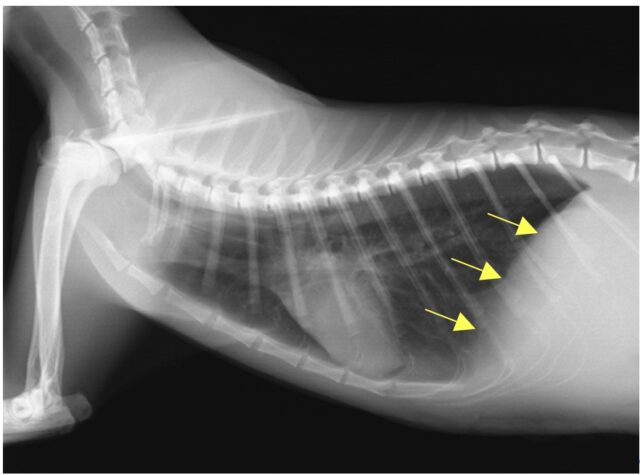

術後5日目の胸部レントゲン写真では、逸脱していた臓器がお腹の中に戻り、正常な横隔膜ライン(矢印)が確認できます。